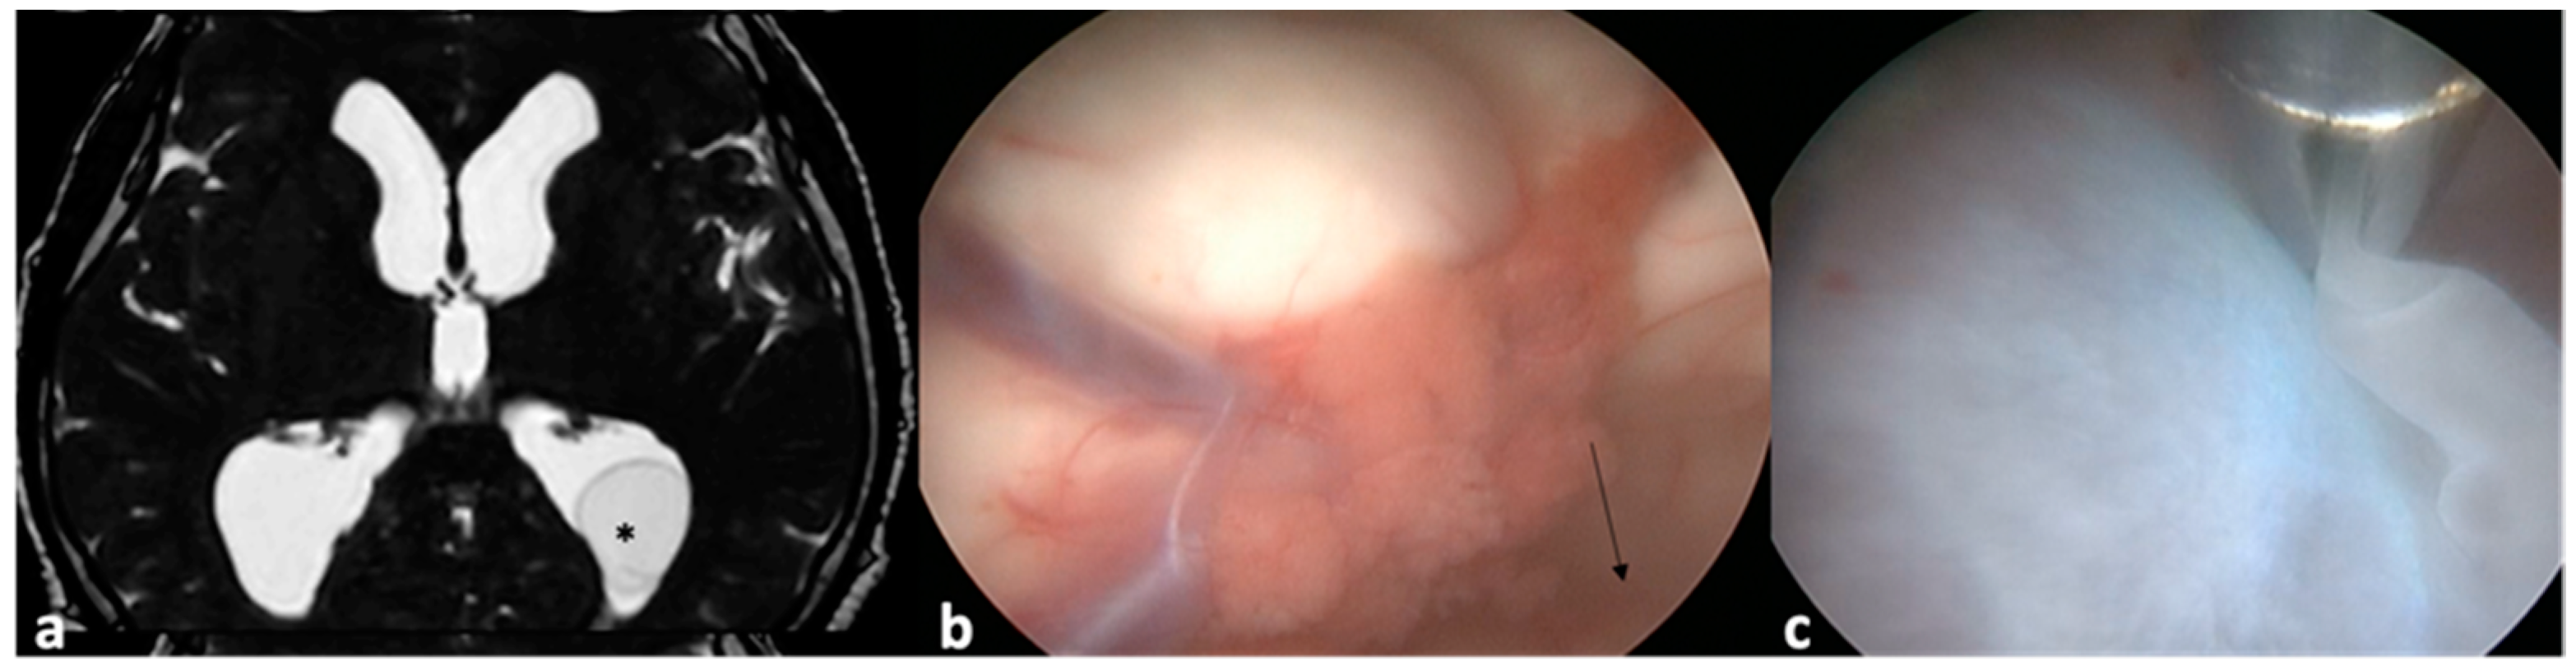

- Husain, M.; Jha, D.K.; Rastogi, M.; Husain, N.; Gupta, R.K. Neuro-endoscopic Management of Intraventricular Neurocysticercosis (NCC). Acta Neurochir. 2007, 149, 341–346. [Google Scholar] [CrossRef]

- Torres-Corzo, J.G.; Tapia-Pérez, J.H.; Vecchia, R.R.; Chalita-Williams, J.C.; Sánchez-Aguilar, M.; Sánchez-Rodríguez, J.J. Endoscopic Management of Hydrocephalus Due to Neurocysticercosis. Clin. Neurol. Neurosurg. 2010, 112, 11–16. [Google Scholar] [CrossRef] [PubMed]

- Proaño, J.V.; Torres-Corzo, J.; Rodríguez-Della Vecchia, R.; Guizar-Sahagun, G.; Rangel-Castilla, L. Intraventricular and Subarachnoid Basal Cisterns Neurocysticercosis: A Comparative Study Between Traditional Treatment Versus Neuroendoscopic Surgery. Child’s Nerv. Syst. 2009, 25, 1467–1475. [Google Scholar] [CrossRef] [PubMed]

- Goel, R.K.; Ahmad, F.U.; Vellimana, A.K.; Suri, A.; Chandra, P.S.; Kumar, R.; Sharma, B.S.; Mahapatra, A.K. Endoscopic Management of Intraventricular Neurocysticercosis. J. Clin. Neurosci. 2008, 15, 1096–1101. [Google Scholar] [CrossRef] [PubMed]

- Zhenye, L.; Chuzhong, L.; Xuyi, Z.; Songbai, G.; Peng, Z.; Jiwei, B.; Lei, C.; Xinsheng, W. Ventriculoscopic Approach for Intraventricular Neurocysticercosis: A Single Neurosurgical Center’s Experience. World Neurosurg. 2017, 107, 853–859. [Google Scholar] [CrossRef]

- Kaif, M.; Husain, M.; Ojha, B.K. Endoscopic Management of Intraventricular Neurocysticercosis. Turk. Neurosurg. 2019, 29, 59–65. [Google Scholar]

- Zymberg, S.T. Neurocysticercosis. World Neurosurg. 2013, 79, S24.e5–S24.e8. [Google Scholar] [CrossRef]

- Singh, S.; Marutirao, R.; Deora, H.; Das, K.K.; Bhaisora, K.S.; Sardhara, J.; Parab, A.; Mehrotra, A.; Srivastava, A.K.; Jaiswal, S.; et al. Endoscopic Route for Excision of Intraventricular Neurocysticercosis: Light At the End of the Tunnel. World Neurosurg. 2019, 125, e74–e81. [Google Scholar] [CrossRef] [PubMed]